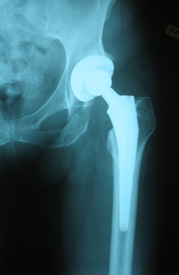

Hip Replacement Surgery

Nowadays hip replacement surgery has become a commonplace procedure.Total hip replacement (THR) is a surgical procedure that relieves pain from most kinds of hip arthritis, improving the quality of life for the large majority of patients who undergo the operation.

Hip Replacement